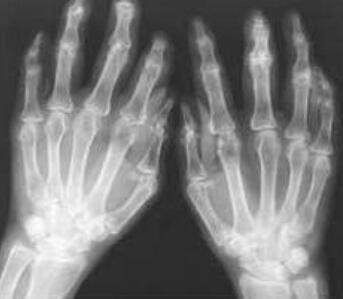

王怀庆主任安排王先生采用系统的三层诊断后,确诊王先生是类风湿性关节炎中晚期,并且有的关节开始尺偏等情况。需要立即开始治疗,以阻断病情继续发展成严重的畸形等问题,随后便制定治疗计划开始治疗。 ...[详细]

李先生从小患有遗传性类风湿,只是小时候症状不明显。后来渐渐就发现自己的手关节出现疼痛,仅靠诊所开的药物控制,体内产生耐药性后,病情恶化,表现为手指肿痛严重,出现膝关节肿胀、手指畸形现象。多次治...[详细]

来院后,我院类风湿医生王怀庆主任立即为高女士安排检查。检查后发现高女士双手的近端还有指间及关节处会有关节肿胀的现象,并且双腕肿胀现象比较严重,下蹲困难,活动受限;最后确诊为类风湿性关节炎。...[详细]